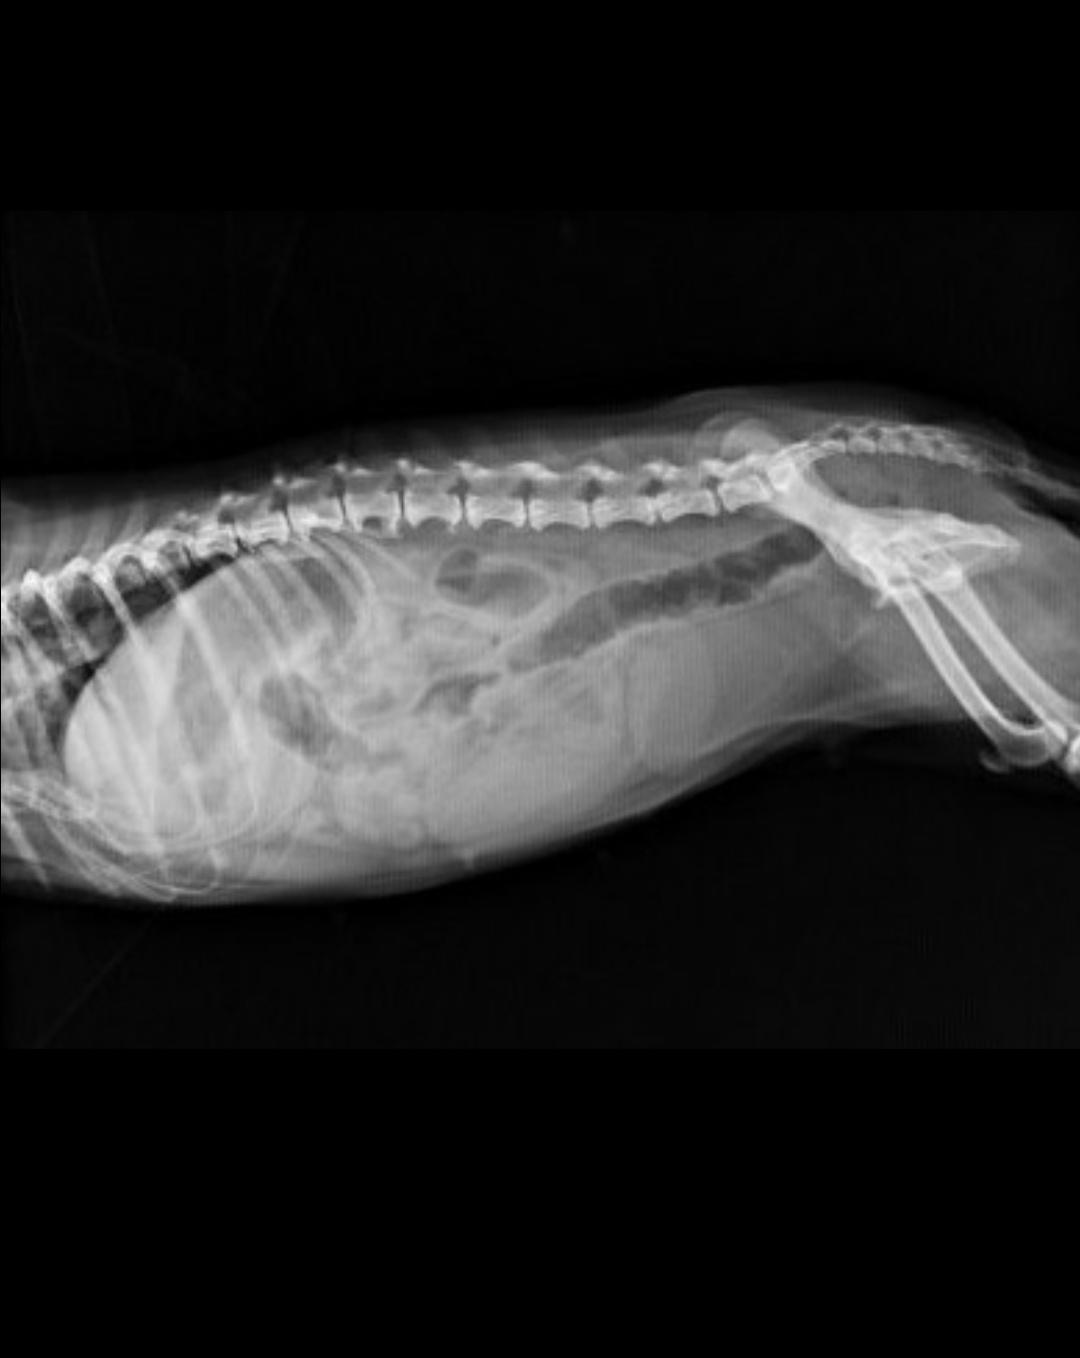

正常子宫和蓄脓后的子宫对比

- 腹部x光:会在脊椎靠下一点,腹中部靠上一点看到香肠样的子宫,密度增大。